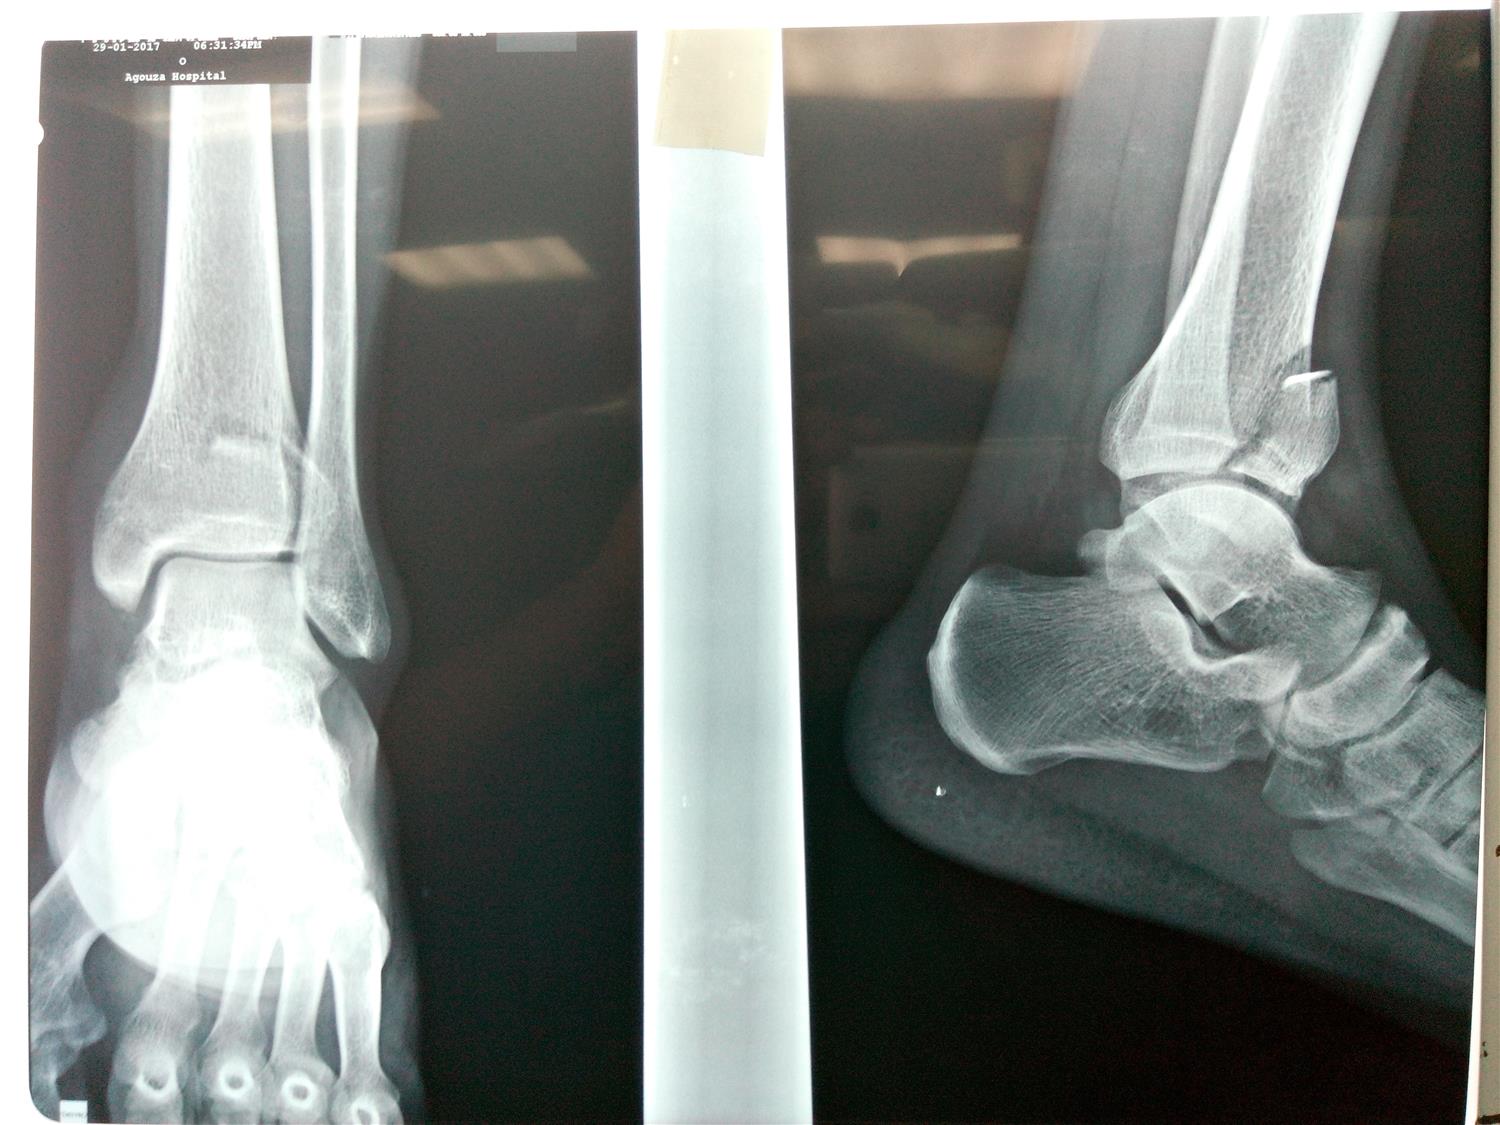

Footballers Ankle Orthobullets . Ankle sprains are the most common injuries in sports and recreational activity, accounting for 40% of all athletic injuries,. He says that prior to symptom development, he was at soccer. Ankle sprains are very common twisting injuries to the ankle that are the most common reason for missed athletic participation. First termed footballer’s ankle by mcmurray in 1950, ami is a common cause of. Diagnosis is made with plain. Chronic ankle pain in football players is most frequently caused by formation of talar and/or tibial osteophytes at the anterior part of. Diagnosis can be made clinically with swelling and. The spurs can form at the bottom end of the joint on the. High ankle sprain & syndesmosis injuries are traumatic injuries that affect the distal tibiofibular ligaments and most commonly occur due to sudden external rotation of the ankle. Ankle fractures are very common injuries to the ankle which generally occur due to a twisting mechanism. Footballer’s ankle, also known as anterior ankle impingement, occurs because bony spurs forms at the front of the ankle joint.

Chronic ankle pain in football players is most frequently caused by formation of talar and/or tibial osteophytes at the anterior part of. Ankle sprains are very common twisting injuries to the ankle that are the most common reason for missed athletic participation. The spurs can form at the bottom end of the joint on the. Diagnosis can be made clinically with swelling and. First termed footballer’s ankle by mcmurray in 1950, ami is a common cause of. Ankle sprains are the most common injuries in sports and recreational activity, accounting for 40% of all athletic injuries,. He says that prior to symptom development, he was at soccer. Footballer’s ankle, also known as anterior ankle impingement, occurs because bony spurs forms at the front of the ankle joint. Ankle fractures are very common injuries to the ankle which generally occur due to a twisting mechanism. High ankle sprain & syndesmosis injuries are traumatic injuries that affect the distal tibiofibular ligaments and most commonly occur due to sudden external rotation of the ankle.

Footballers Ankle Orthobullets First termed footballer’s ankle by mcmurray in 1950, ami is a common cause of. Ankle fractures are very common injuries to the ankle which generally occur due to a twisting mechanism. Ankle sprains are the most common injuries in sports and recreational activity, accounting for 40% of all athletic injuries,. The spurs can form at the bottom end of the joint on the. Diagnosis is made with plain. Diagnosis can be made clinically with swelling and. Chronic ankle pain in football players is most frequently caused by formation of talar and/or tibial osteophytes at the anterior part of. He says that prior to symptom development, he was at soccer. High ankle sprain & syndesmosis injuries are traumatic injuries that affect the distal tibiofibular ligaments and most commonly occur due to sudden external rotation of the ankle. First termed footballer’s ankle by mcmurray in 1950, ami is a common cause of. Ankle sprains are very common twisting injuries to the ankle that are the most common reason for missed athletic participation. Footballer’s ankle, also known as anterior ankle impingement, occurs because bony spurs forms at the front of the ankle joint.

Footballer's Ankle Diagnosis, Causes, Symptoms and Treatment Footballers Ankle Orthobullets Chronic ankle pain in football players is most frequently caused by formation of talar and/or tibial osteophytes at the anterior part of. Ankle sprains are very common twisting injuries to the ankle that are the most common reason for missed athletic participation. High ankle sprain & syndesmosis injuries are traumatic injuries that affect the distal tibiofibular ligaments and most commonly. Footballers Ankle Orthobullets.

Footballer's Ankle Diagnosis, Causes, Symptoms and Treatment Footballers Ankle Orthobullets He says that prior to symptom development, he was at soccer. The spurs can form at the bottom end of the joint on the. Diagnosis can be made clinically with swelling and. Ankle fractures are very common injuries to the ankle which generally occur due to a twisting mechanism. Chronic ankle pain in football players is most frequently caused by. Footballers Ankle Orthobullets.

Footballer's Ankle Diagnosis, Causes, Symptoms and Treatment Footballers Ankle Orthobullets First termed footballer’s ankle by mcmurray in 1950, ami is a common cause of. Ankle sprains are very common twisting injuries to the ankle that are the most common reason for missed athletic participation. Ankle sprains are the most common injuries in sports and recreational activity, accounting for 40% of all athletic injuries,. He says that prior to symptom development,. Footballers Ankle Orthobullets.

Footballer's Ankle Diagnosis, Causes, Symptoms and Treatment Footballers Ankle Orthobullets First termed footballer’s ankle by mcmurray in 1950, ami is a common cause of. Diagnosis can be made clinically with swelling and. Ankle fractures are very common injuries to the ankle which generally occur due to a twisting mechanism. Ankle sprains are very common twisting injuries to the ankle that are the most common reason for missed athletic participation. Ankle. Footballers Ankle Orthobullets.